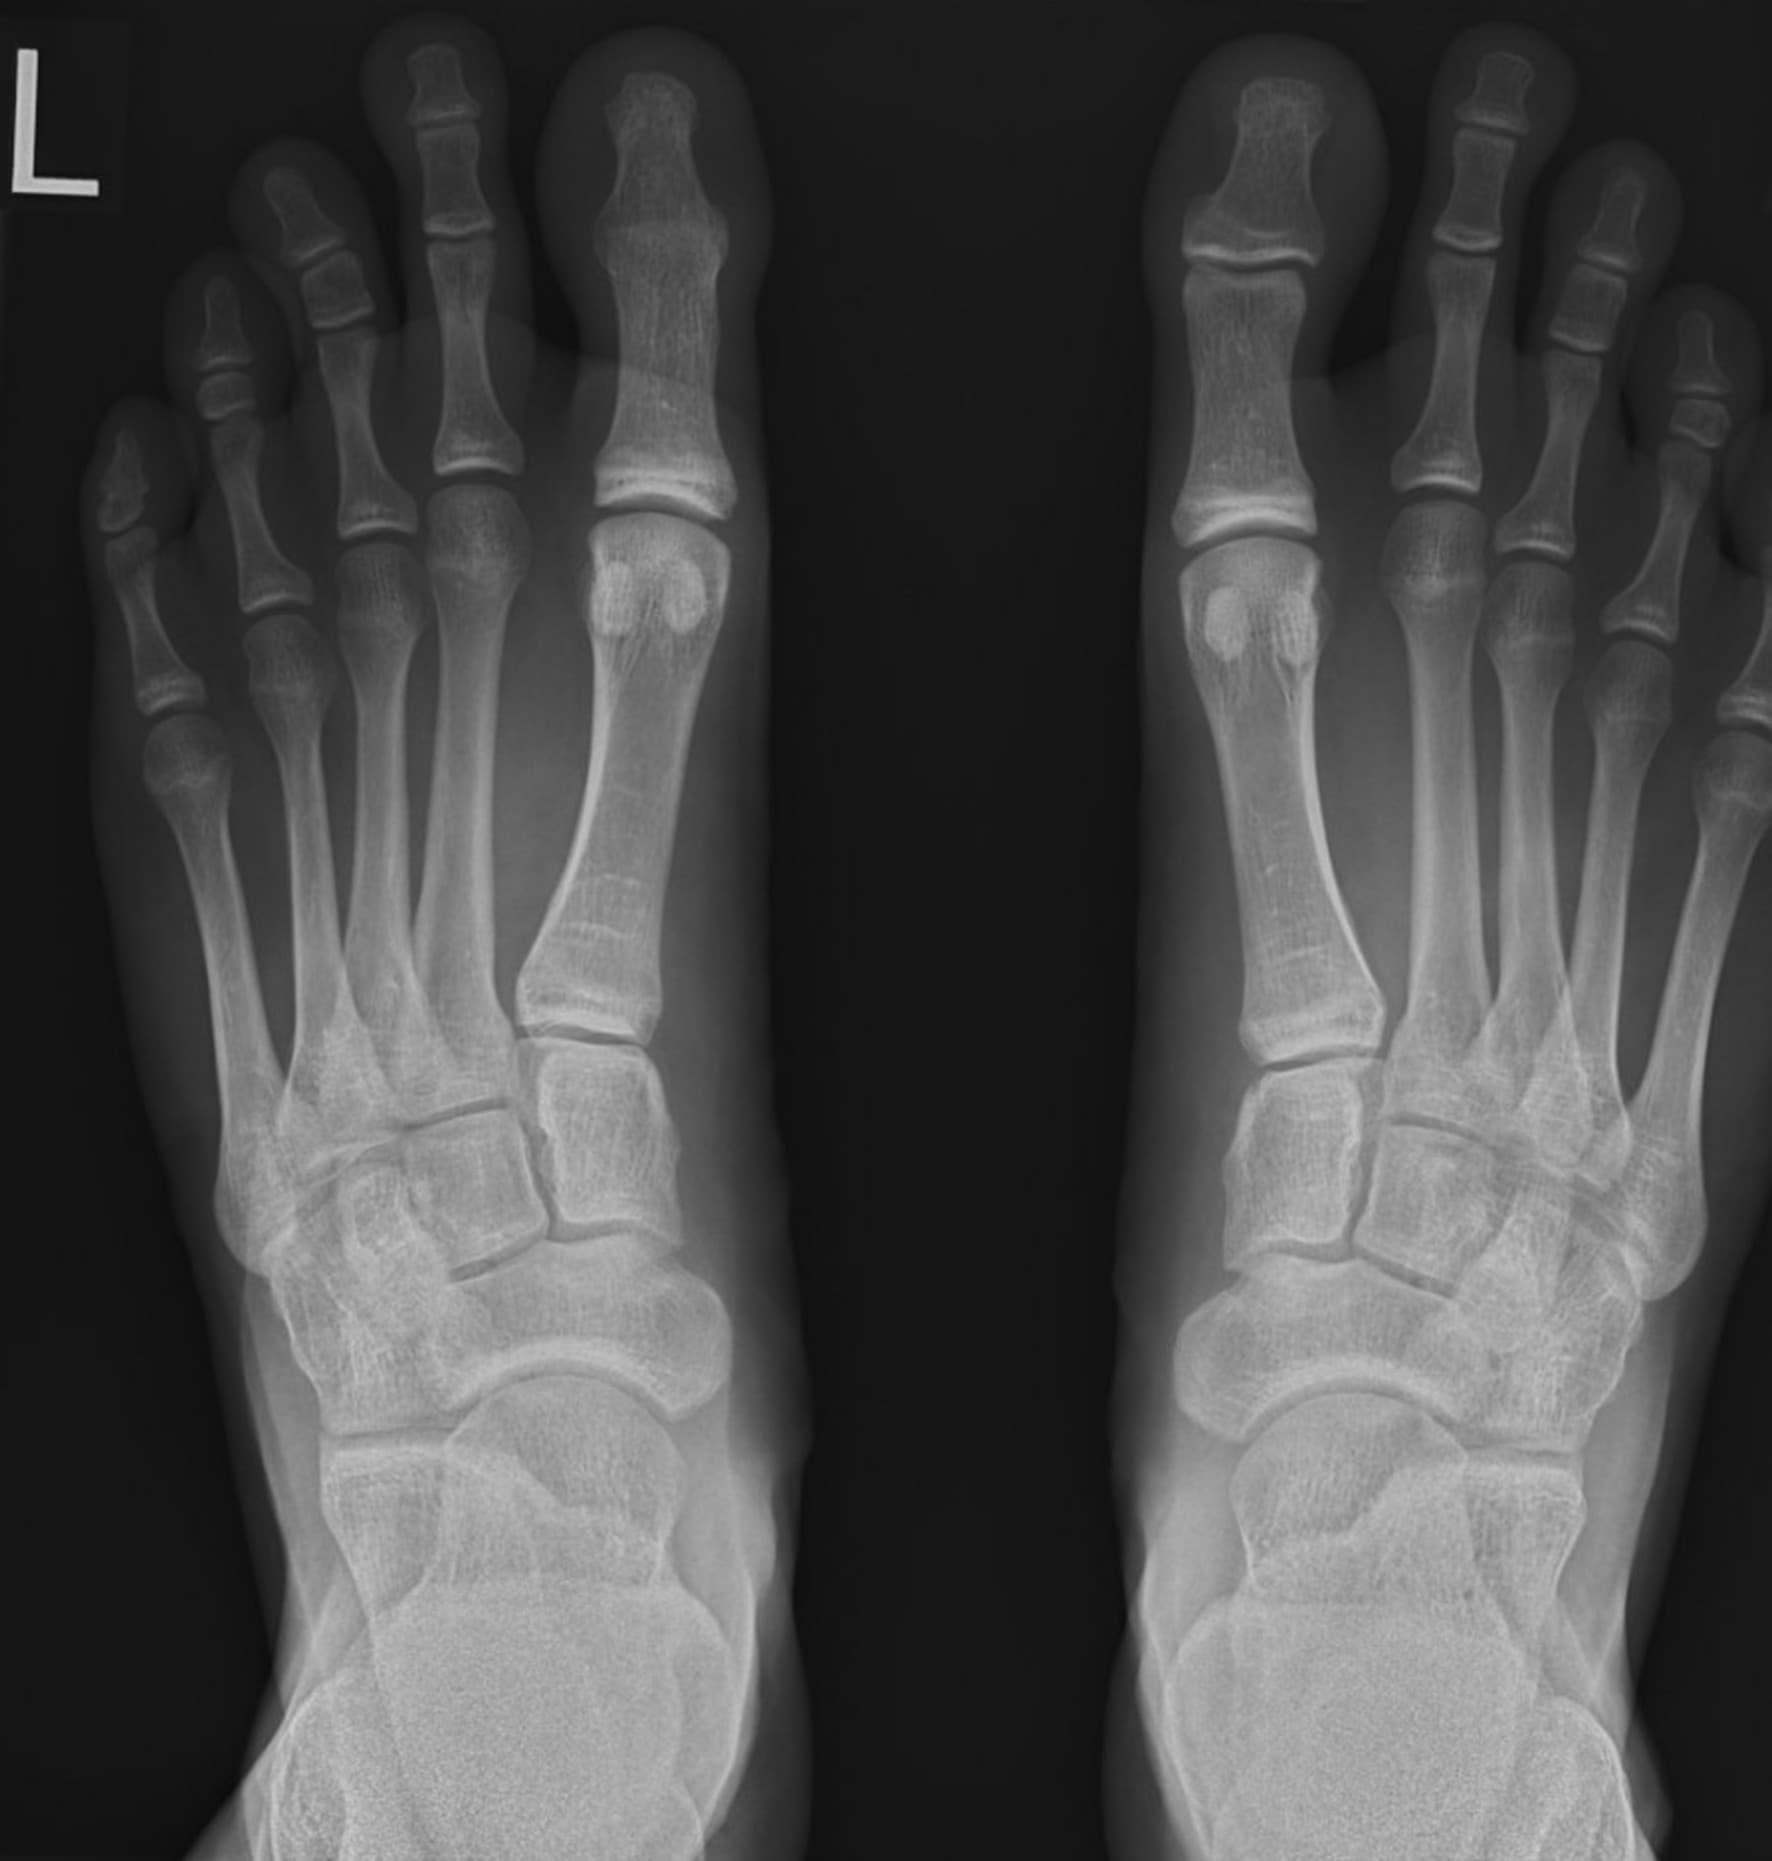

En ung mand er henvist grundet nedsat bevægelse og belastningsrelateret gener ved sport over venstre 1. tå. Røntgen viser ankylose af venstre tås yderled, men årsagen hertil skal findes år tilbage.

Ugens billede illustrerer derfor en sjælden senfølge, nemlig ankylose af venstre 1. tås proksimale og distale phalanx sekundært til en postoperativ infektion. Postoperativ infektion udgør den største komplikation til neglekirurgi med en incidens på 3-5% [3, 4]. Lignede tilstande er ikke tidligere beskrevet i litteraturen. Enkle lignende tilfælde på fingrenes yderled er beskrevet, men her grundet forsinket primær behandling – kirurgisk revision og antibiotika [5].